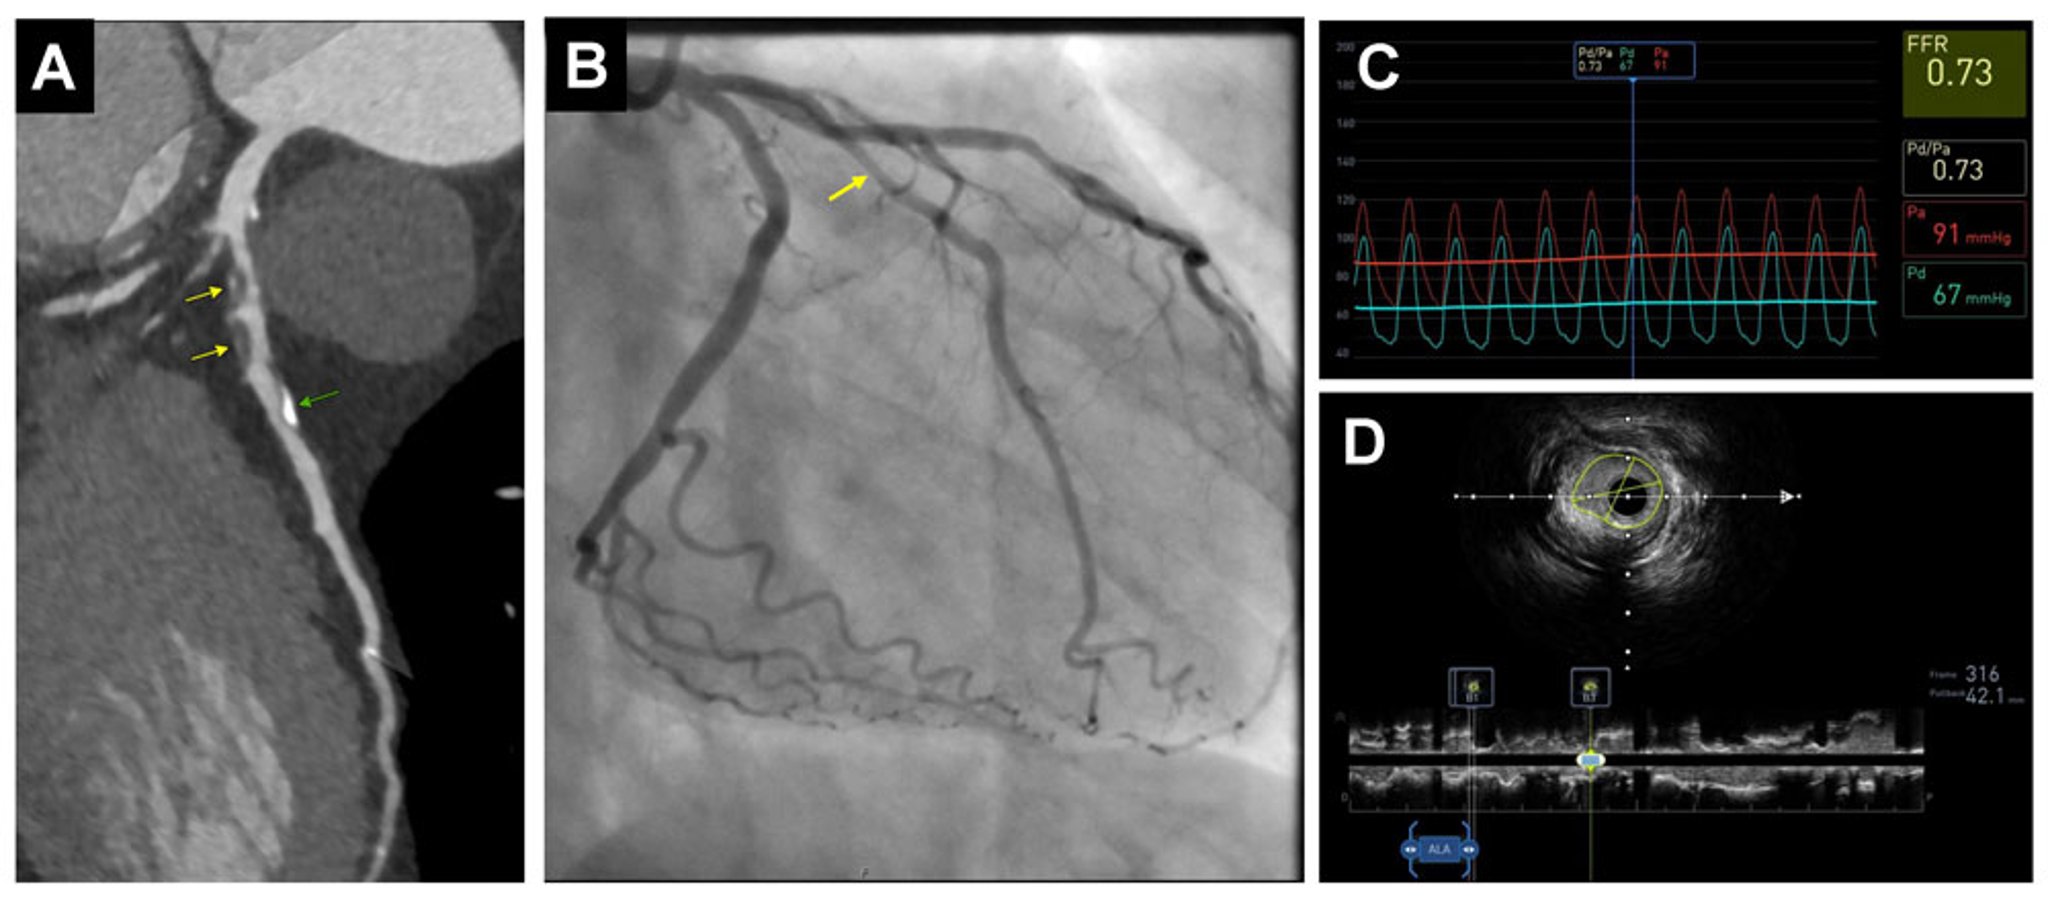

A(左侧):冠状动脉CT血管造影显示广泛的混合斑块,包括钙化斑块(绿色箭头)和以非钙化为主的斑块(黄色箭头)。

B(中):有创冠状动脉造影证实中度左前降管腔狭窄(箭头),通过分数血流储备(FFR)评估血流动力学意义显著(< 0.80)(C,右上)。

D(右下):血管内超声(IVUS)引导的血运重建术。管腔狭窄的程度在横截面中可见。